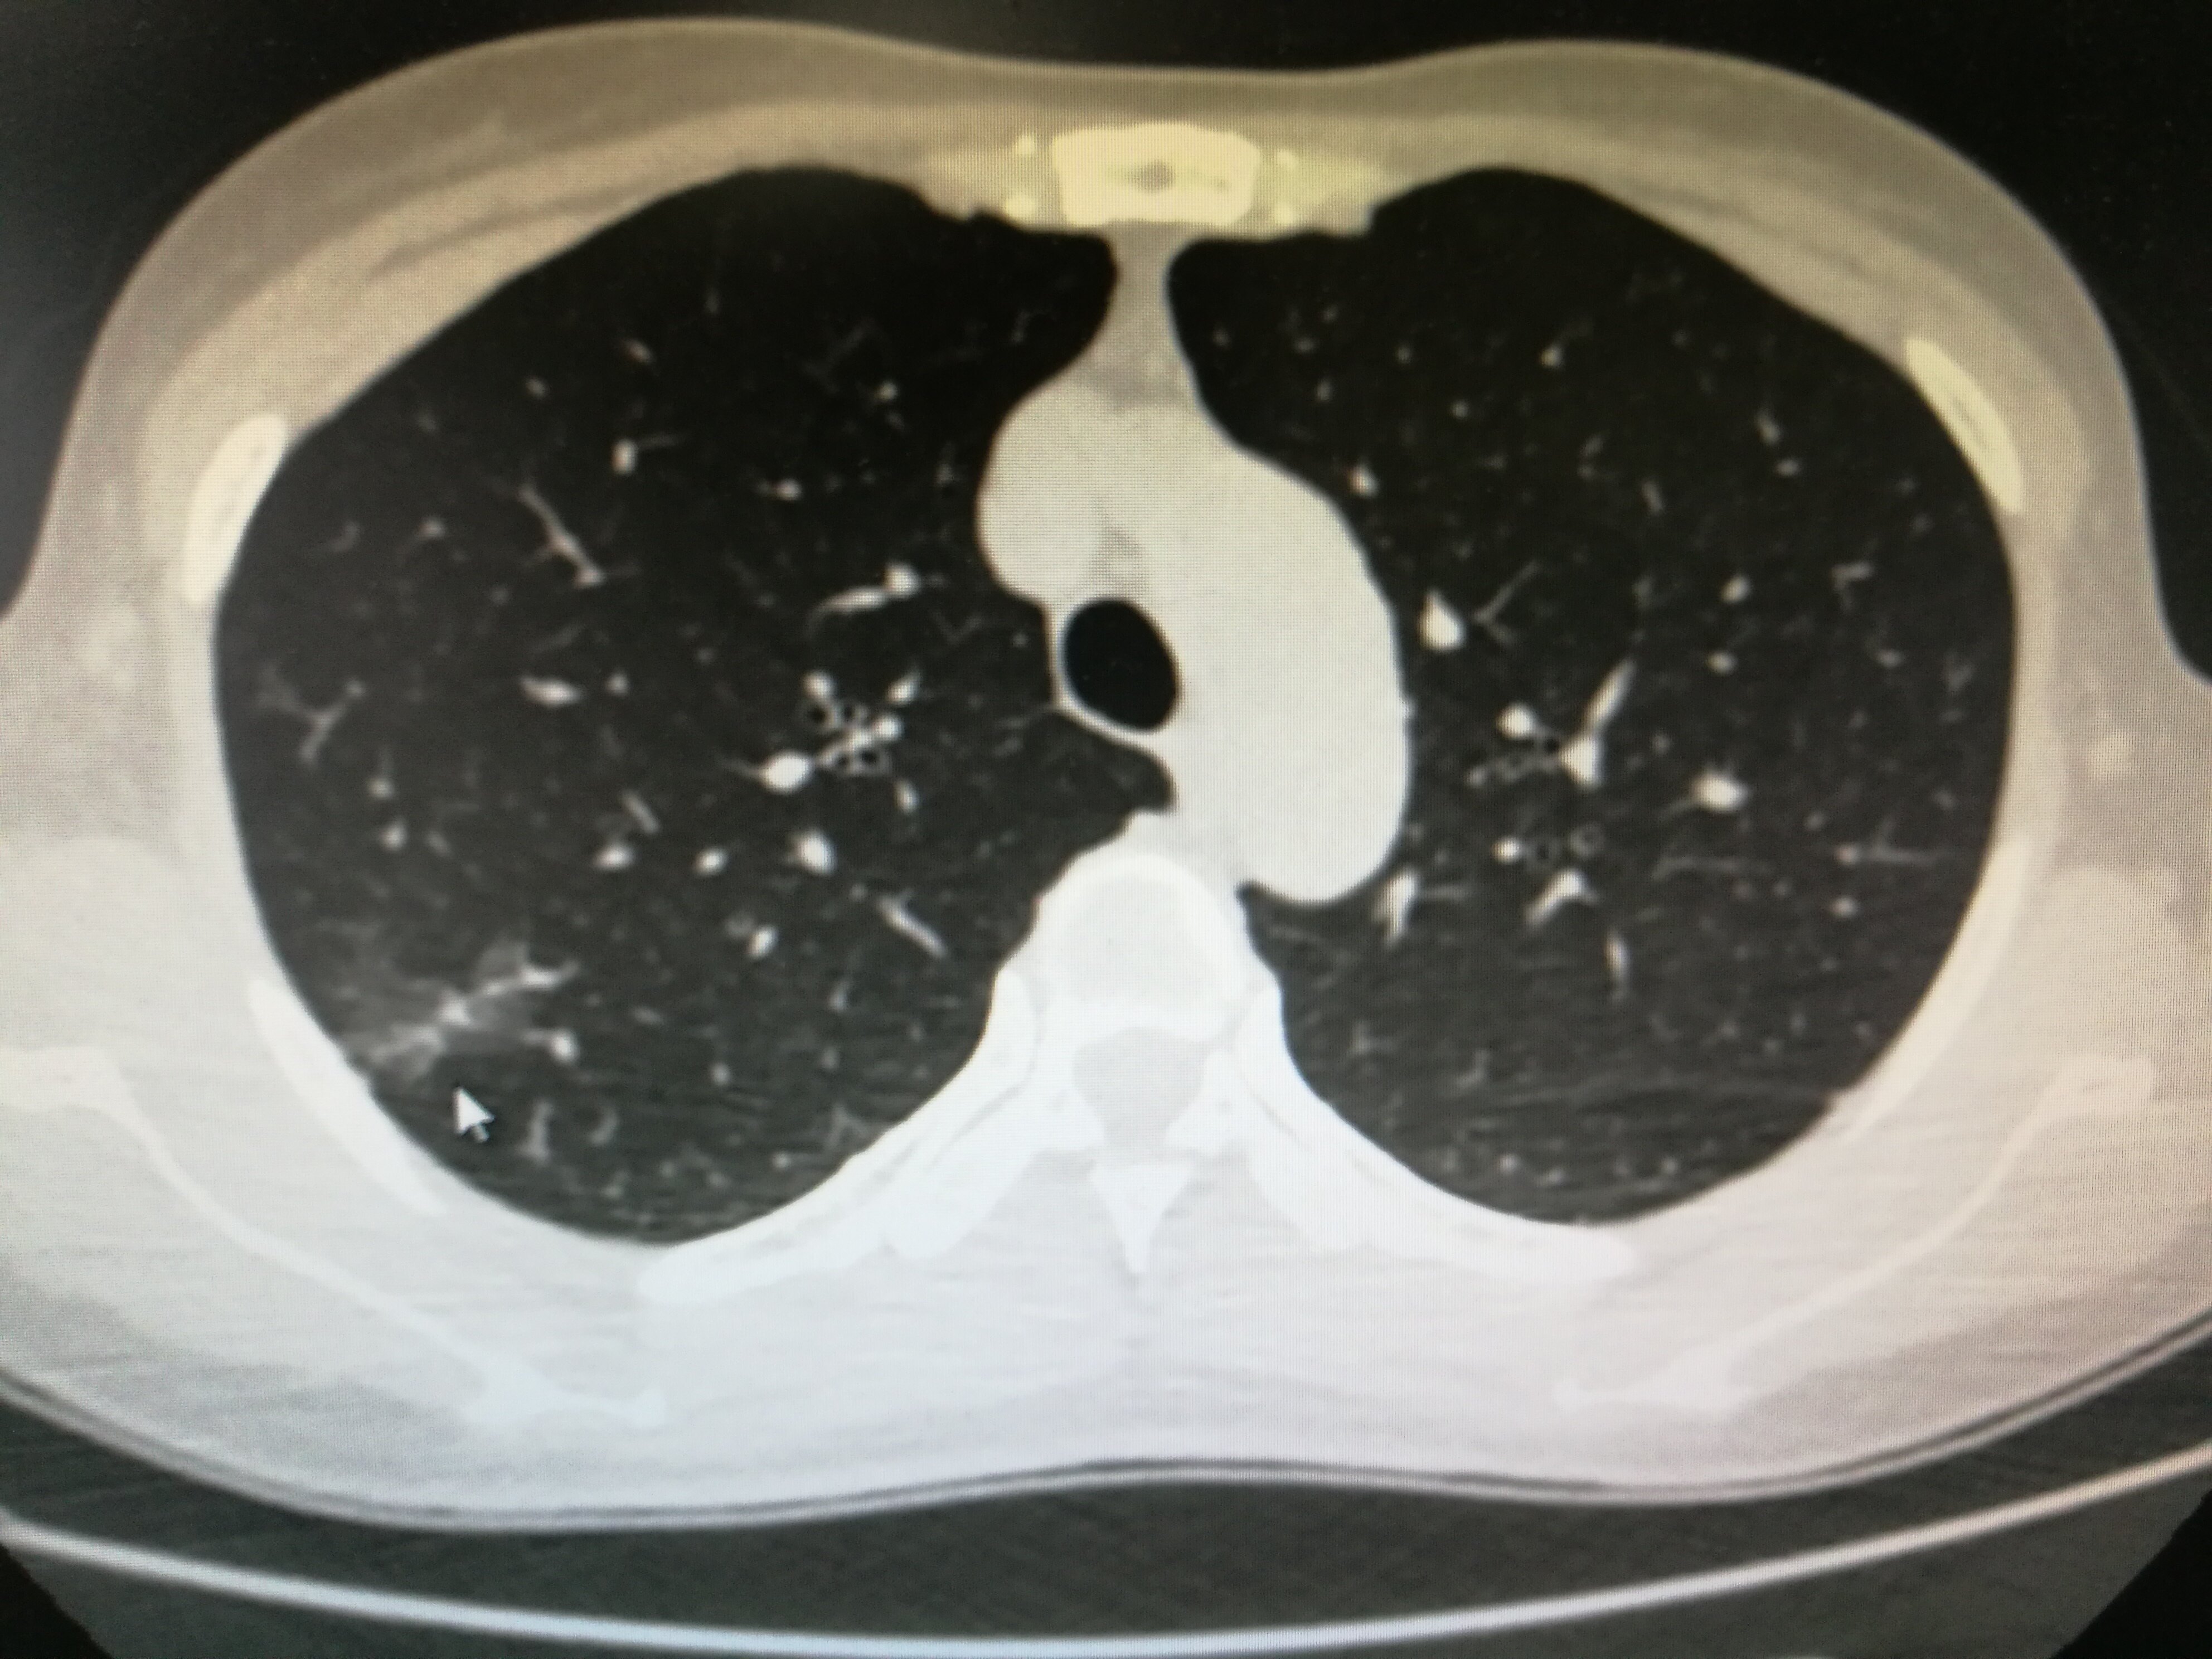

如果发现肺部结节,注意结节的大小和性质。小于5mm的结节,多为良性结节,与炎症、吸烟或其他理化刺激有关,不必担心,但要定期随访或复查。若结节改变,出现包膜、分支或增大,或累及胸膜,应及时进一步检查,排除恶性病变的可能。如果结节大于8mm,应进行支气管镜检查或经皮穿刺活检。如果肺部结节在短时间内出现明显的快速生长或恶性CT影像学特征,则需要手术切除。

肺部结节大部分是良性的,不会癌变。但患者应注意定期观察,检查结节的变化。如果发现结节病变越来越大,外观看起来恶性,一定要根据病情的严重程度及时手术。极少数肺癌结节会癌变,比如瘢痕癌。这种情况经常发生在有过肺结核或慢性肺病留下疤痕的人身上,尤其是长期吸烟、有肿瘤家族史的人。必须警惕肺部结节癌变的可能。查出肺部结节是从影像学得出的结论,但由于其病因复杂,与肺癌、肺部疾病等有关,其中肺癌最为严重。